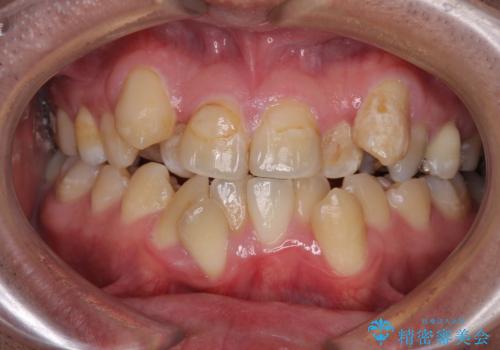

- 上下の八重歯やデコボコを気にして来院された患者様です。

上下ともに八重歯が顕著であったので、上下左右第一小臼歯4本を抜歯し、ワイヤー装置にて矯正治療を行うこととしました。

デコボコが強いことが原因で歯間部に汚れが溜まりやすい状態でしたが、矯正前にできる限り汚れが少なくなるようにブラッシングなどの指導を行い、口腔状態が改善された後にワイヤー装置を装着することとしました。